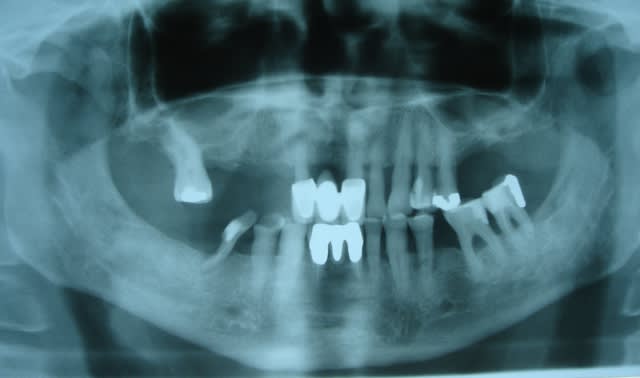

Pp vous remet bien le bonjour à tous et part en vacances après s'être bcp trop amusé ces temps-ci...

PS Désolé pour les kissing implants en 12 13 ...